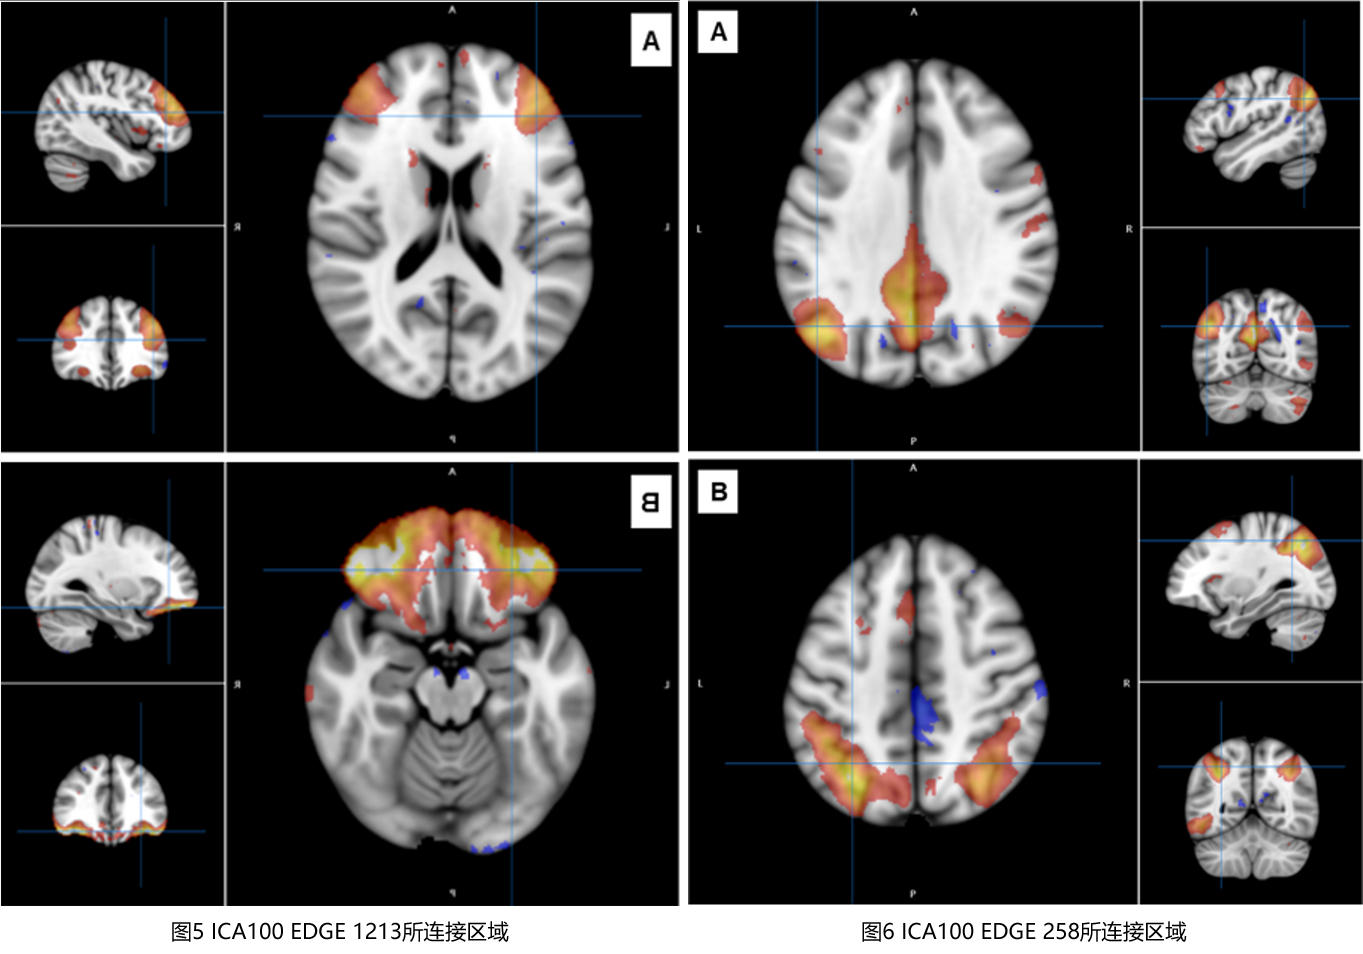

在孟德尔随机化分析中,研究结果显示OSA可能导致左侧颞下沟区域面积以及rs-fMRI连接网络中的ICA100 edge 893、edge 951、edge 1213等区域显著降低。同时,OSA还可能导致右侧额下回三角形部分平均厚度、右侧绒毡层方向离散度指数(OD)以及rs-fMRI连接网络中的ICA100 edge 258等区域显著增加(图2)。rs-fMRI连接网络中的ICA100 edge 893、edge 951、edge 1213以及ICA100 edge 258所连接的区域如图3-图6所示。